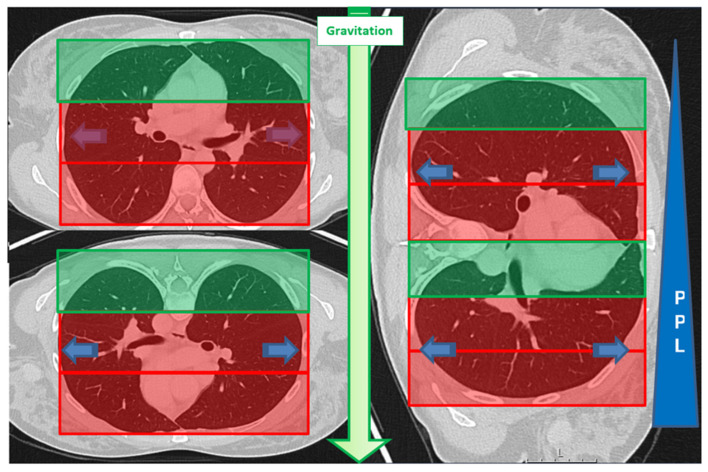

Background/objectives: The risk of hemorrhage during CT-guided lung biopsy has not been systematically studied in cases where ground-glass opacities (GGO) are present in the access route or when biopsies are performed in highly perfused, dependent lung areas. While patient positioning has been studied for pneumothorax prevention, its role in minimizing hemorrhage risk remains unexplored. This study aimed to determine whether GGOs in the access route and biopsies in dependent lung areas are risk factors for pulmonary hemorrhage during CT-guided lung biopsy.

Methods: A retrospective analysis was conducted on 115 CT-guided lung biopsies performed at a single center (2020-2023). Patients were categorized based on post-interventional hemorrhage exceeding 2 cm (Grade 2 or higher). We evaluated the presence of GGOs in the access route and biopsy location (dependent vs. non-dependent areas) using chi square, Fisher's exact, and Mann-Whitney U tests. Univariate and multivariate logistic regression analyses were conducted to evaluate risk factors for pulmonary hemorrhage.

Results: Pulmonary hemorrhage beyond 2 cm occurred in 30 of 115 patients (26%). GGOs in the access route were identified in 67% of these cases (p < 0.01), and hemorrhage occurred more frequently when biopsies were performed in dependent lung areas (63% vs. 40%, p = 0.03). Multivariable analysis showed that GGOs in the access route (OR 5.169, 95% CI 1.889-14.144, p = 0.001) and biopsies in dependent areas (OR 4.064, 95% CI 1.477-11.186, p < 0.001) independently increased hemorrhage risk.

Conclusions: GGOs in the access route and dependent lung area biopsies are independent risk factors for hemorrhage during CT-guided lung biopsy.